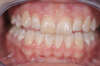

APRES

Réalisation d'une facette céramique sur l'incisive droite qui présentait un composite disgracieux. La dent est légèrement préparée. Une dent provisoire est mise en place entre les deux séances. Un collage est enfin réalisée après validation esthétique.